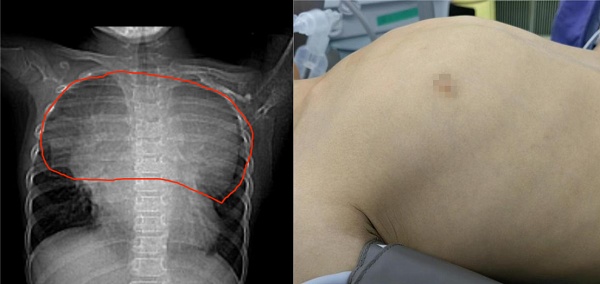

左图:红色圈出范围为胸腔内肿瘤占据的空间;右图:乐乐的胸廓明显凸起

7岁男孩乐乐(化名)胸廓突起,误以为是“鸡胸”,实则隐藏一个巨大肿瘤,占据胸腔一半,好似一个“炸弹”,贴近心脏和大血管“雷区”,随时有生命危险。

于是,他们带着乐乐继续就诊,CT检查竟然发现乐乐胸腔里有一个非常大的肿瘤,几乎占据一半的胸腔空间。乐乐爸爸妈妈瞬间就慌了,带着乐乐四处求医。

然而,多家医院的医生都告诉乐乐父母,肿瘤太大了,就像一个炸弹,随时会引发病情的大爆炸,需要切除;但同时肿瘤紧贴着心脏和大血管,处于“雷区“,切除肿瘤时极易出现大血管或者心脏破裂,一旦伤及心脏和大血管,随时会危及生命,手术难度非常大,可以说是几乎无法手术。